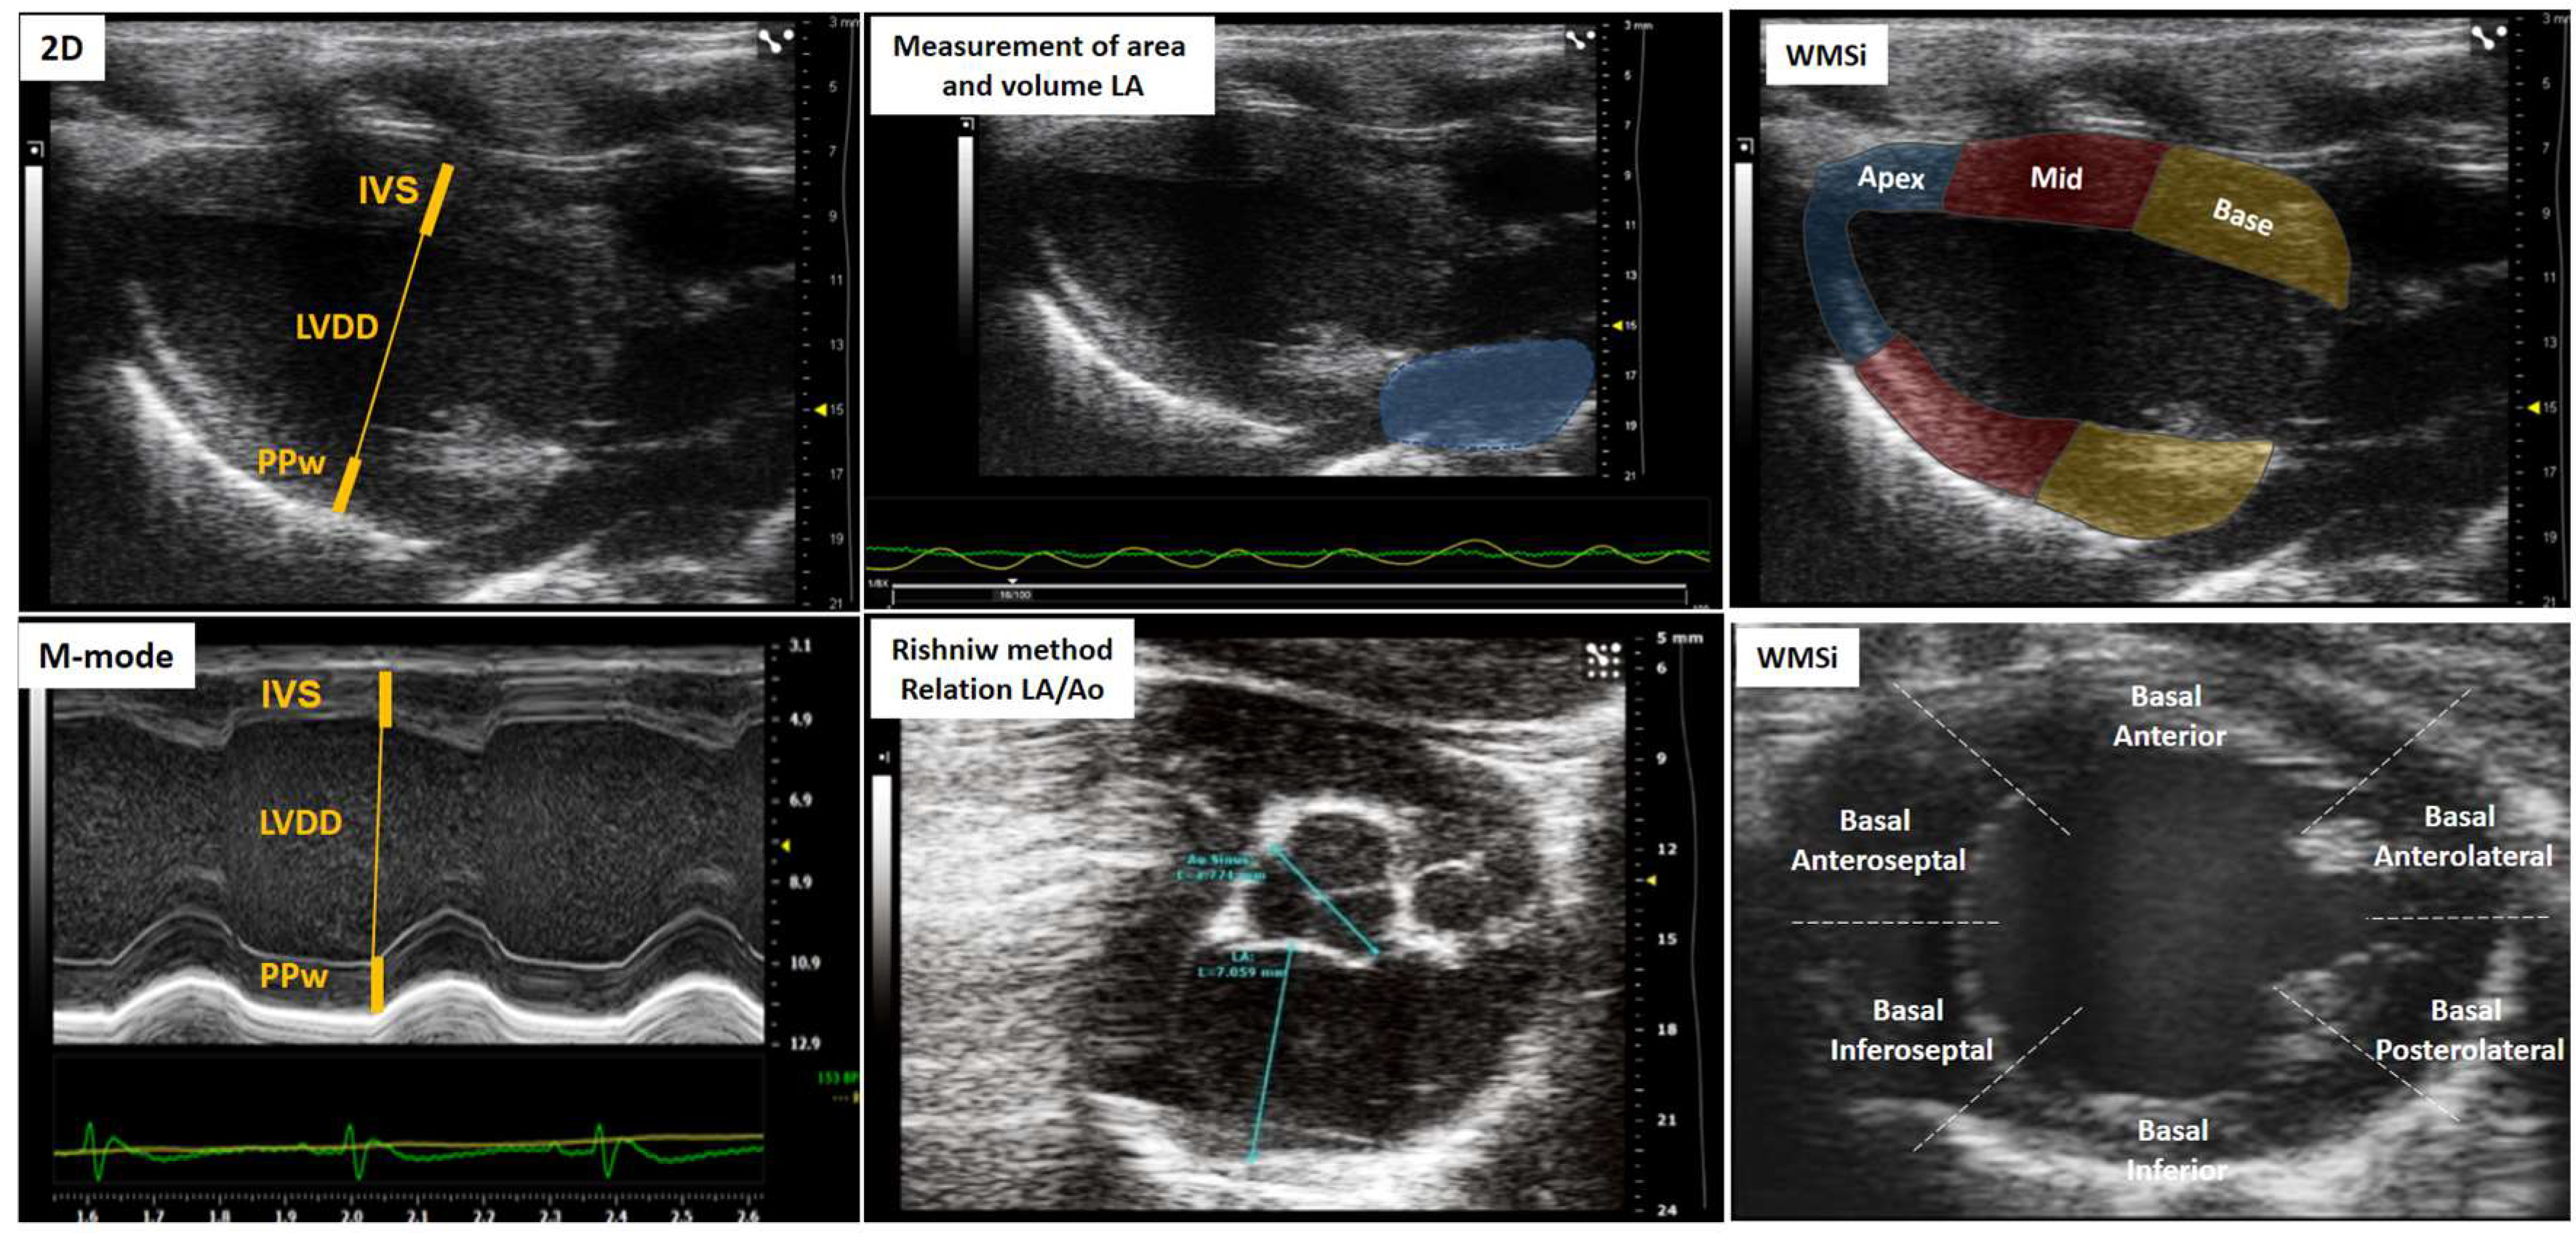

| Left atrium | Left ventricle | Right ventricle | Overload and congestion |

|---|---|---|---|

| LA volume | IVS | RV basal dimension | Pericardial effusion |

| LA-area | LVDD | (Apical 4-chamber) | B-lines (Lulmonary congestion) |

| LA-diameter | LVSD | Proximal dimension of the RV outflow tract | ICV collapsibility indices |

| Aort-Dimension | PPw | (Parasternal short axis, anterior to the aortic valve) | (Animal breathing spontaneously) |

| Relation LA/Ao | Relative thickness | Fractional area change RV | IVC distensibility indices |

| LV mass | (Apical 4-chamber) | (Animal on mechanical ventilation) |